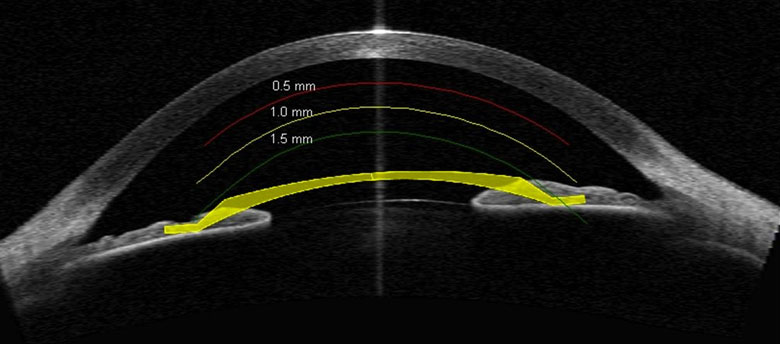

La technique du LASIK consiste à découper une fine lamelle de la cornée, appelée aussi capot cornéen, à l’aide d’un microkératome ou d’un laser femtoseconde.

Ce capot est ensuite soulevé afin d’appliquer le traitement laser, puis reposé et maintenu par adhésion naturelle.